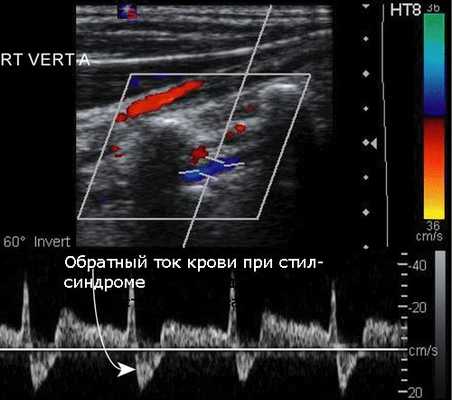

Начальная диагностика для выявления поражения позвоночной артерии на шее проводится с помощью УЗИ с цветовым допплеровским картированием. Ультразвуковое исследование позволяет выявить патологию сосудов у большинства пациентов, однако этот метод зависит от используемой аппаратуры и навыков врача УЗИ. Метод позволяет выявить сужение в шейном отделе позвоночной артерии, структуру атеросклеротической бляшки, характер кровотока по позвоночной артерии. Транскраниальная допплерография (ТКД) применяется для обнаружения внутричерепного стеноза позвоночной артерии. Метод позволяет в 80% случаев выявить нарушение кровотока в базилярной и позвоночных артериях, возможно исследование с детекцией эмболии (переноса кусочков бляшки в мозговые сосуды), что доказывает роль сужения в развитии нарушений мозгового кровообращения.